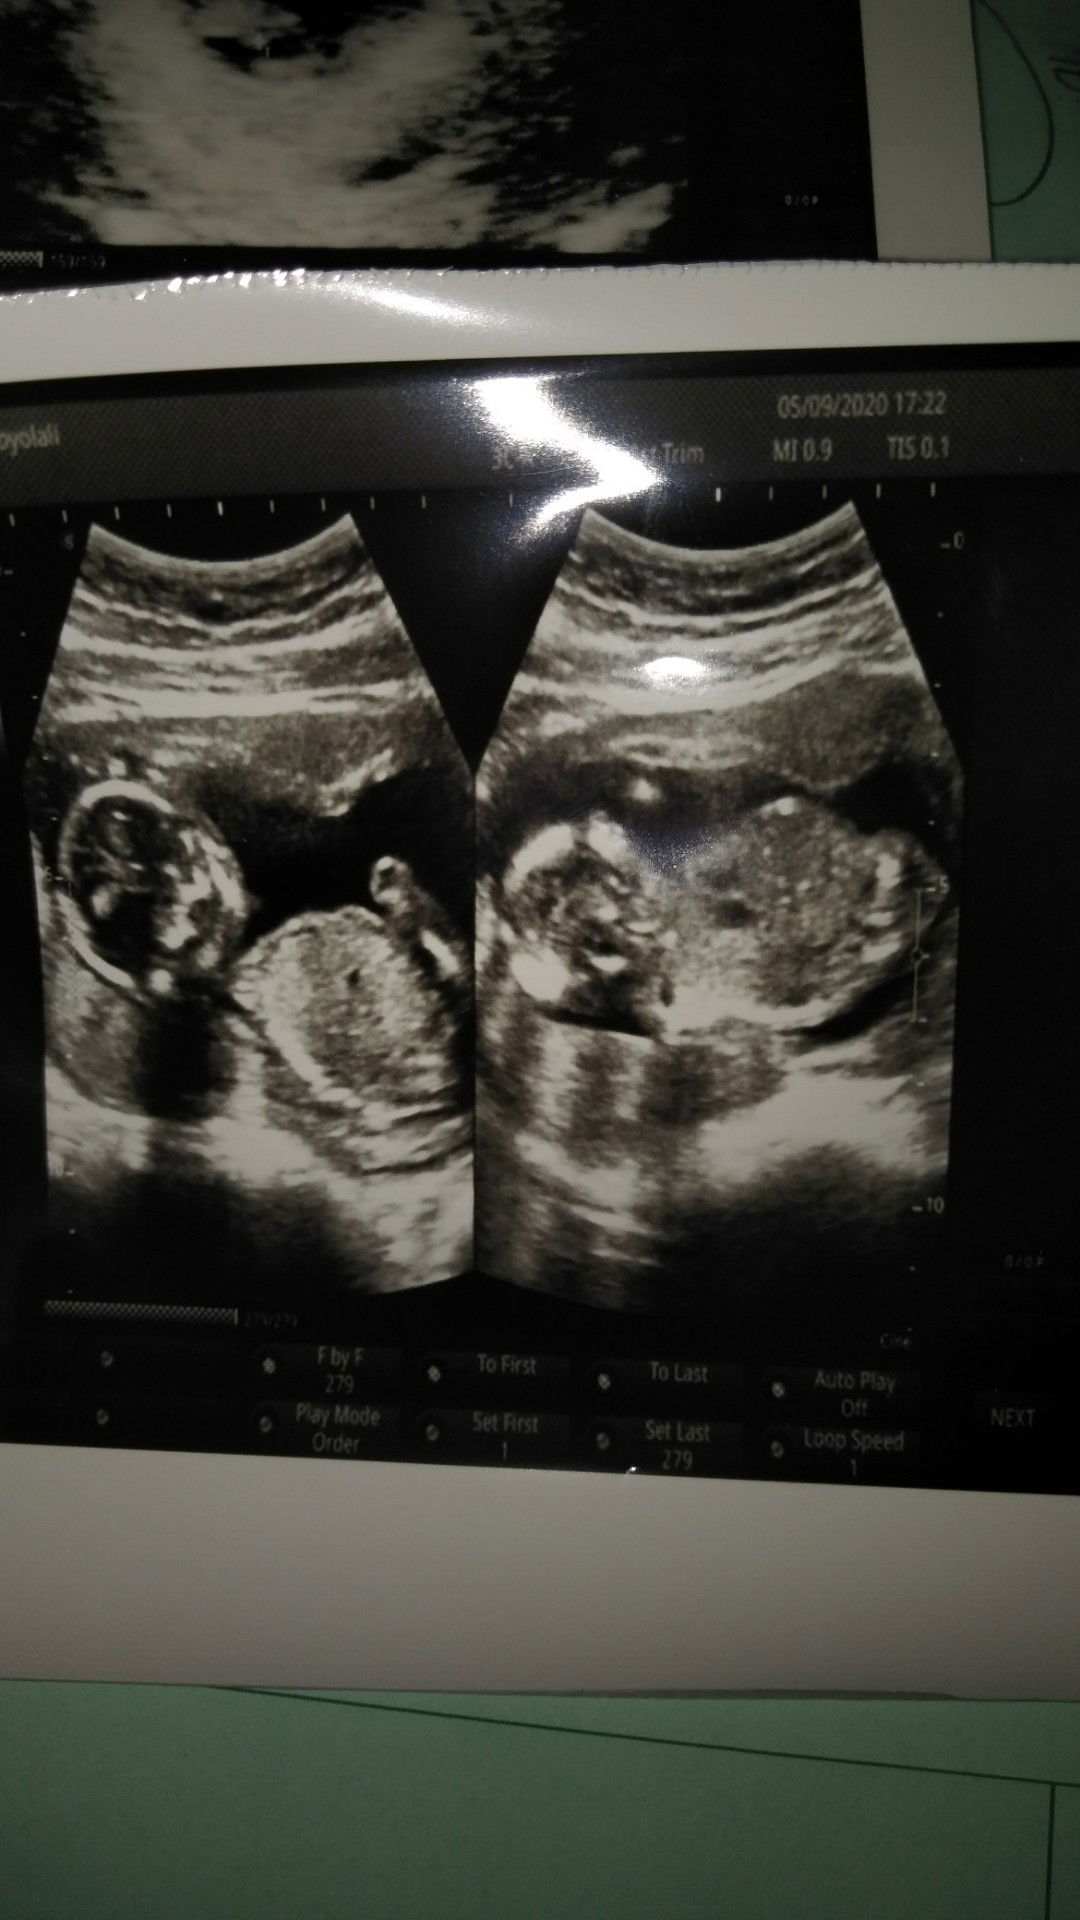

lagi nabung tuk lahiran baby

buat lahiran anak pertama ku

untuk membeli kebutuhan bayi

buat lahiran anak kedua

nabung buat biaya melahirkan

Menyambut kelahiran baby sih

Kperluan bayi

Persalinannya baby